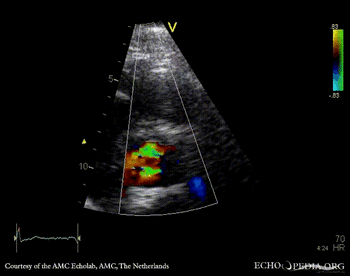

E00418.gif E00419.gif

PLAX: Color Doppler, moderate aortic regurgitation PSAX